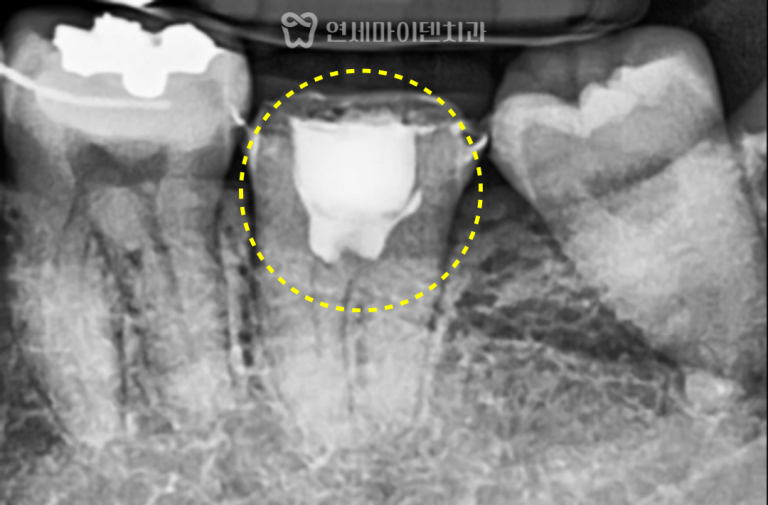

안녕하세요, 소중한 치아를 지키는연세마이덴치과 닥터꼬집입니다. 오늘은 잇몸 고름과 염증때문에타 치과에서 발치 진단을 받았지만, 신경치료를 통해 치아를…